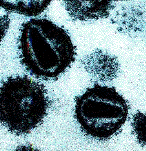

Coronaviruses

enveloped filamentous ssRNA

- Respiratory tract infections,

SARS